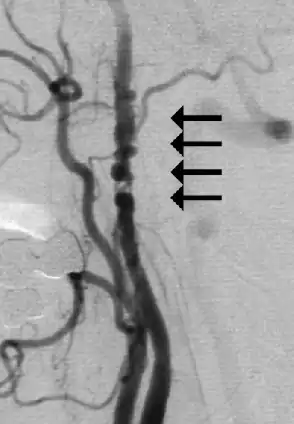

Angiogram showing narrowing of the arteries in the neck in a women with a TIA[1]

Vessels in the head and neck may also be evaluated to look for atherosclerotic lesions that may benefit from interventions, such as carotid endarterectomy. The vasculature can be evaluated through the following imaging modalities: magnetic resonance angiography (MRA), CT angiography (CTA), and carotid ultrasonography/transcranial doppler ultrasonography.[4] Carotid ultrasonography is often used to screen for carotid artery stenosis, as it is more readily available, is noninvasive, and does not expose the person being evaluated to radiation. However, all of the above imaging methods have variable sensitivities and specificities, making it important to supplement one of the imaging methods with another to help confirm the diagnosis (for example: screen for the disease with ultrasonography, and confirm with CTA).[18] Confirming a diagnosis of carotid artery stenosis is important because the treatment for this condition, carotid endarterectomy, can pose significant risk to the patient, including heart attacks and strokes after the procedure.[18] For this reason, the U.S. Preventive Services Task Force (USPSTF) "recommends against screening for asymptomatic carotid artery stenosis in the general adult population".[18] This recommendation is for asymptomatic patients, so it does not necessarily apply to patients with TIAs as these may in fact be a symptom of underlying carotid artery disease (see "Causes and Pathogenesis" above). Therefore, patients who have had a TIA may opt to have a discussion with their clinician about the risks and benefits of screening for carotid artery stenosis, including the risks of surgical treatment of this condition.